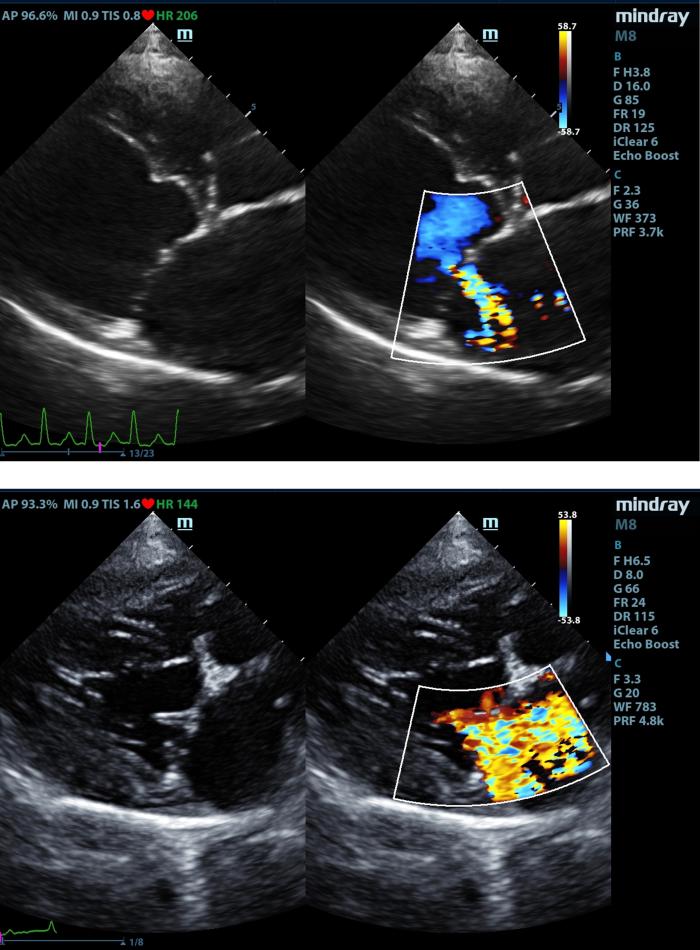

Se han utilizado medidas ecocardiográficas ya publicadas anteriormente. El leaflet-annulus indexx (LAI)es un parámetro para evaluar si existe un ensanchamiento del anillo mitral, se realiza mediante la medición de las valvas anterior (AML) y posterior mitral (PML), además del diámetro antero-posterior del anillo mitral (APL), en la vista paraesternal derecha 4 cámaras en la telesístole cardíaca (Figura 1).

Posteriormente se obtiene este índice mediante la siguiente fórmula: LAI= AML (mm) + PML (mm)]/APL(mm). El área mitral se calcula obteniendo los diámetros de la válvula mitral (AM) en la vista paraesternal derecha transversal a la altura de la válvula mitral, con los diámetros anteroposterior (dAP) y diámetro transcversal (dT) (Figura2) y la fórmula: AM = (π x (dAP/2) x (dT/2))/100. Y por último los diámetros y áreas de las valvas mitrales medidas en la vista paraesternal derecha 4 cámaras durante la diástole (Figura3A-B).

Todas las mediciones ecocardiográficas se han realizado con un equipo Mindray M8, con sondas phase array de diferentes frecuencias (2-11 Hz) según el tamaño del paciente, todos los estudios ecocardiográficos fueron realizados por el autor. Posteriormente los pacientes se han clasificado según la enfermedad cardíaca que presentaban y, por último, se han clasificado en los diferentes grupos de la clasificación de Carpentier aumentada y adaptada.